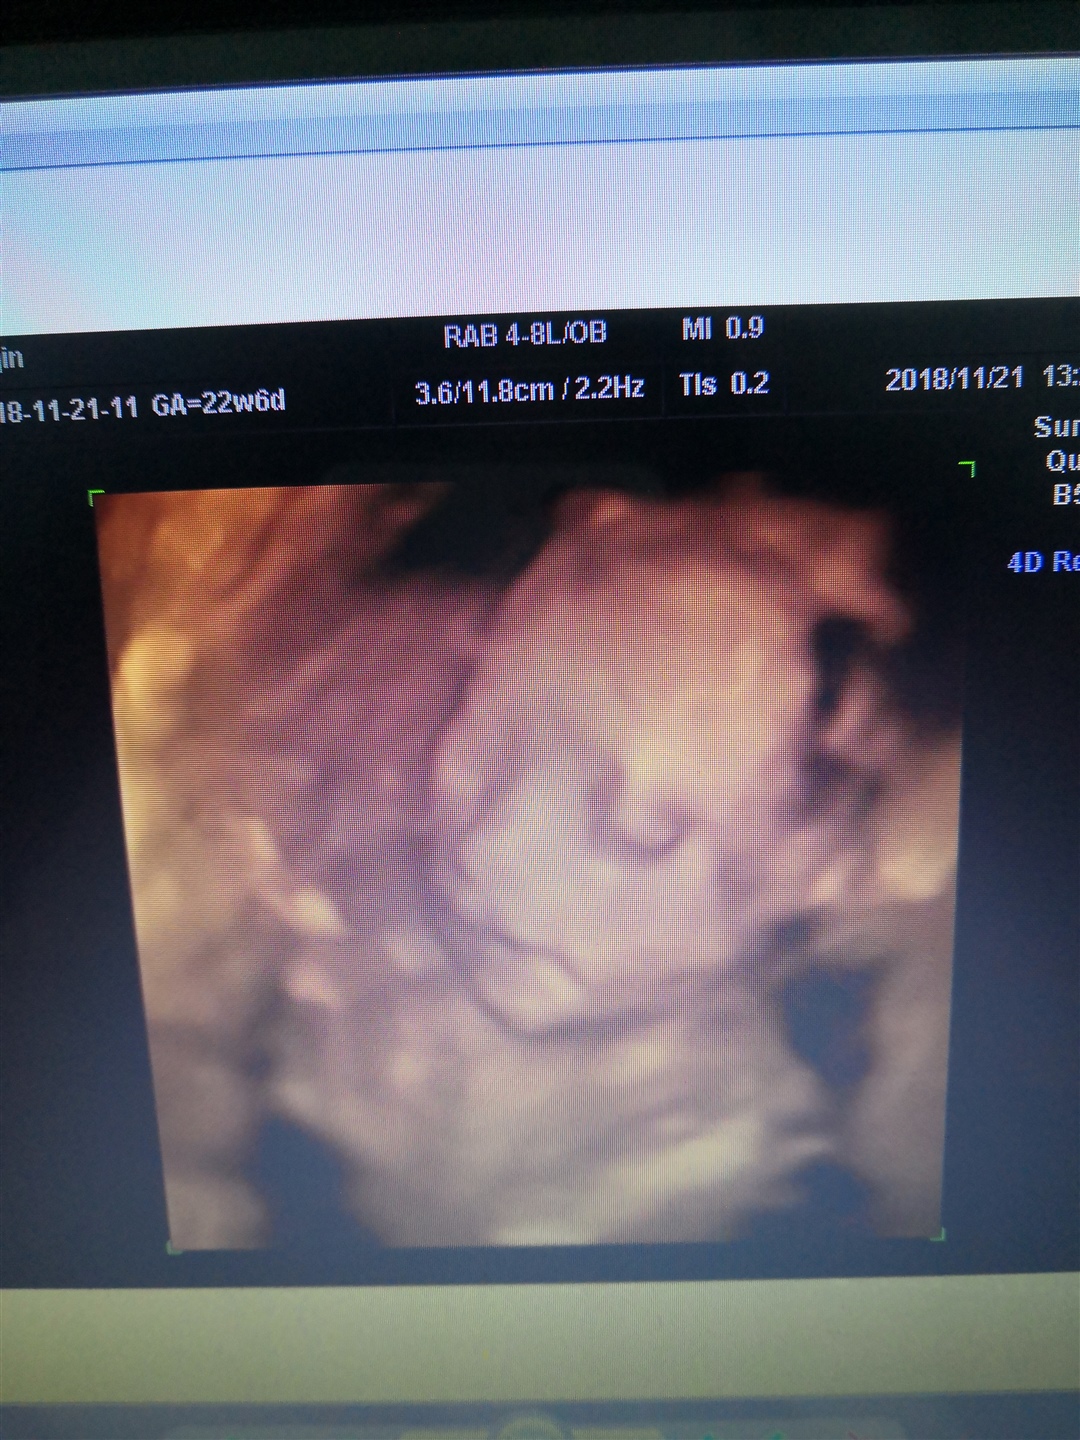

晴吖头~~

女孩样感觉